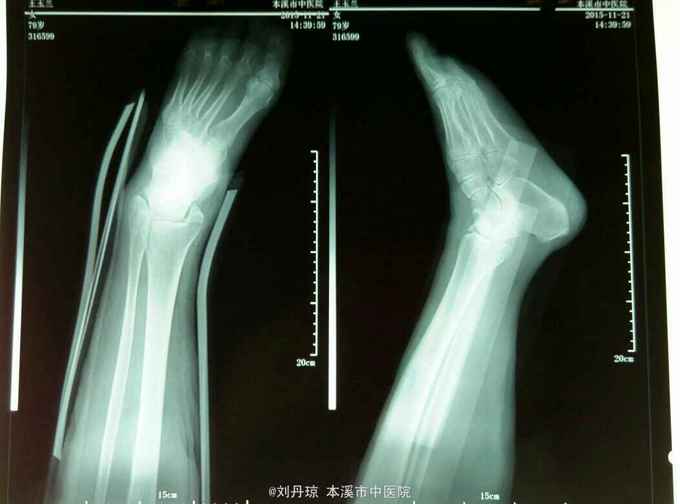

左踝关节畸形,肿胀明显,压痛阳性,左踝关节功能障碍。足背动脉搏动清,足趾活动良好。辅查:DR:左踝关节骨折,三踝骨折移位明显。

诊断:左踝关节骨折 旋后外旋型IV度 治疗:手法整复,活血膏外用,夹板固定。接骨丹口服。

随访1年。讨论:对于踝关节骨折脱位,治疗的目标,是将关节脱位解剖复位。并为此自骨折愈合,最终使踝关节恢复良好的功能。结果与踝关节解剖重建的好坏直接相关。治疗的手段,不外乎,包括保守治疗和手术治疗两种,近三十年来,由于人们对生活质量和功能结果的要求的提高。结果评价的标准,发生了变化,保守治疗,和手术治疗的适应症,有了明显的变化。闭合复位,对于某些,类型的环关节骨折脱位很难,达到和保持器解剖复位,为了丢失和反复长福,将影响治疗效果。另外长时间的制动,也可导致失用性骨质疏松,和踝关节僵硬。但这些通过适当的方法都是可以避免的。本例患者,经一次复位达到,维持解剖复位。本例患者由于全身条件的影响,患者不愿接受手术。故采用保守治疗。